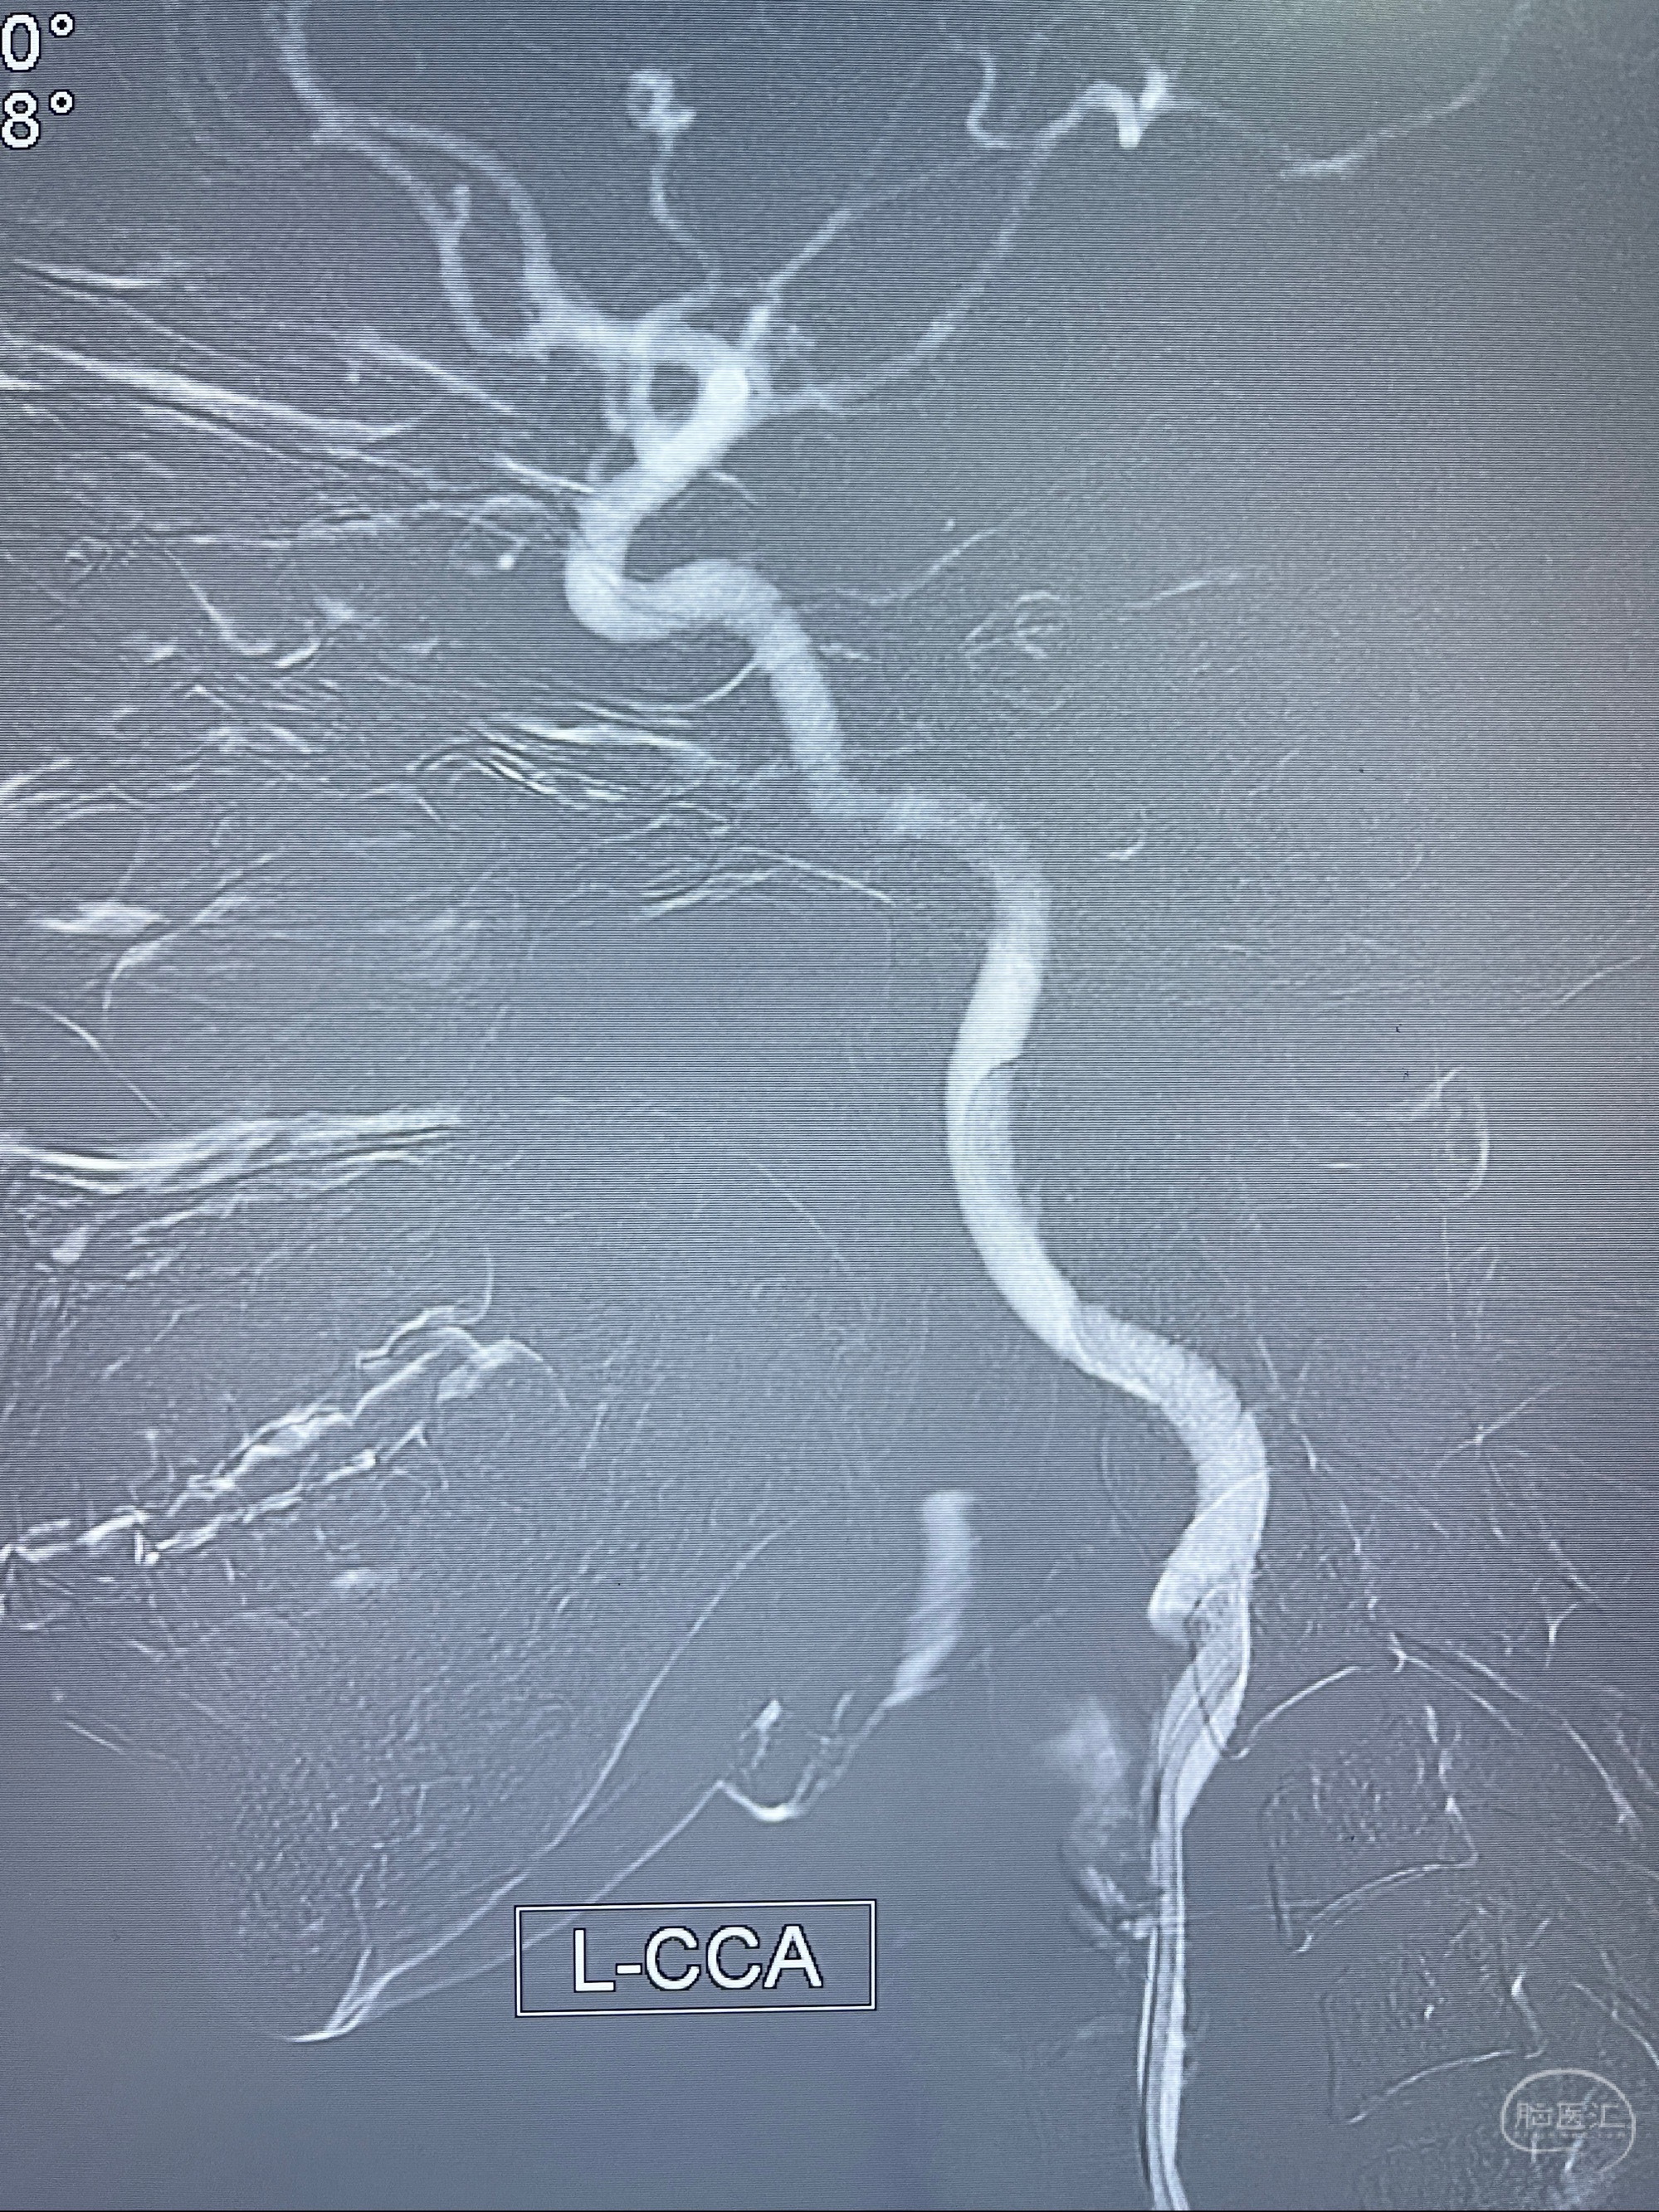

2023-08-14DSA:

左侧大脑中动脉动脉瘤,约2.6-2.8-3.4-2mm大小(瘤颈部、瘤体部、瘤高)